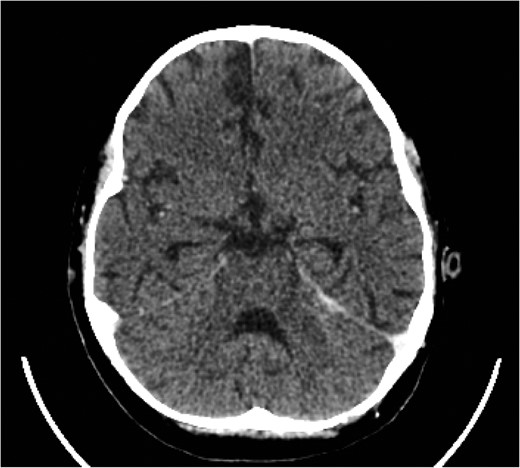

The cerebellar brain abscess was drained surgically, with pus sent for microscopy and culture. This returned gram negative coliform organisms and pus cells. The antibiotic therapy was modified to account for the new microbial sensitivities. The appearances of both the brain and chest improved over the next 10 days with complete resolution of the intracerebral abscesses and thrombosis (Fig. 8). There was a slower resolution of the chest. The patient was discharged from our institution after 16 weeks.

Eventual complete resolution of the brain abscesses and sinus/ IJV thrombosis.